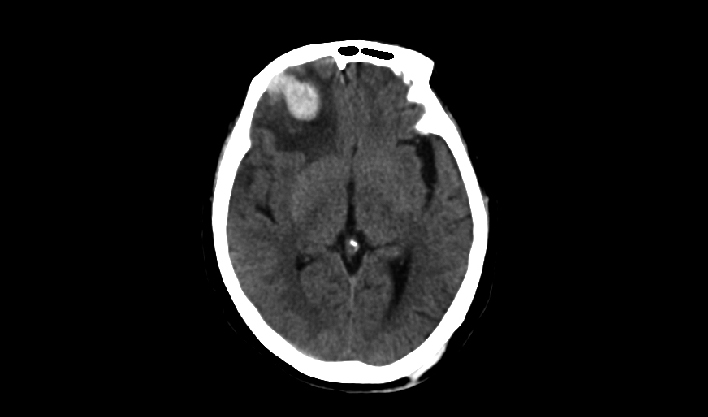

La matriz de reconstrucción de 1024*1024 amplía los datos de la imagen cuatro veces. Combinado con imágenes de corte fina, incluso las lesiones más invisibles son claramente visibles.